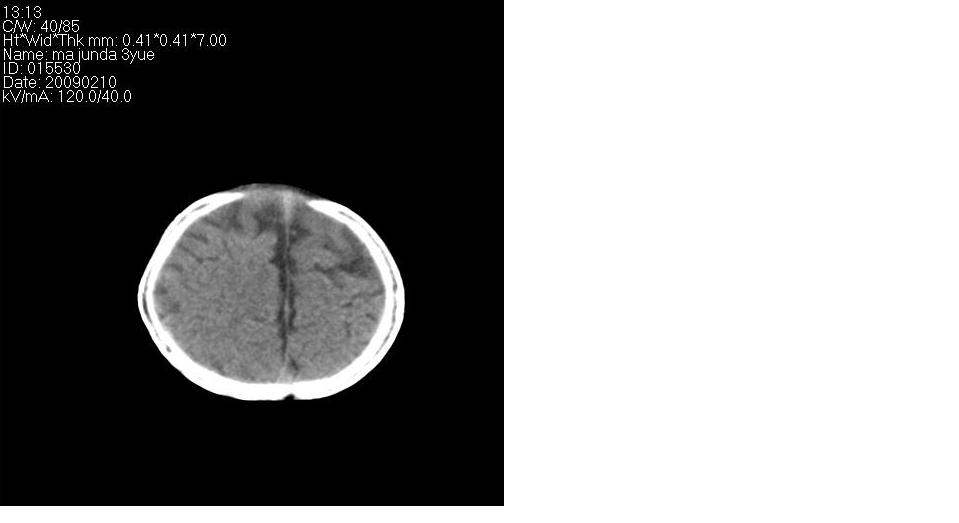

标题: PED1744:颅脑CT平扫

男 3个月,头大,颈软,头向后仰。

外部性脑积水

考虑外部性脑积水。

脑外间隙增宽,未见明显异常。

脑外间隙增宽,余未见明显异常。

脑外间隙增宽,现在好像有人说是一种发育性的交通性脑积水

蛛网膜增宽,外部性脑积水?

外部性脑积水(也就是诸位说的脑外间隙增宽);脑实质内未见异常密度灶,脑室系统无扩张,建议随访,毕竟临床症状听着怪吓人的。